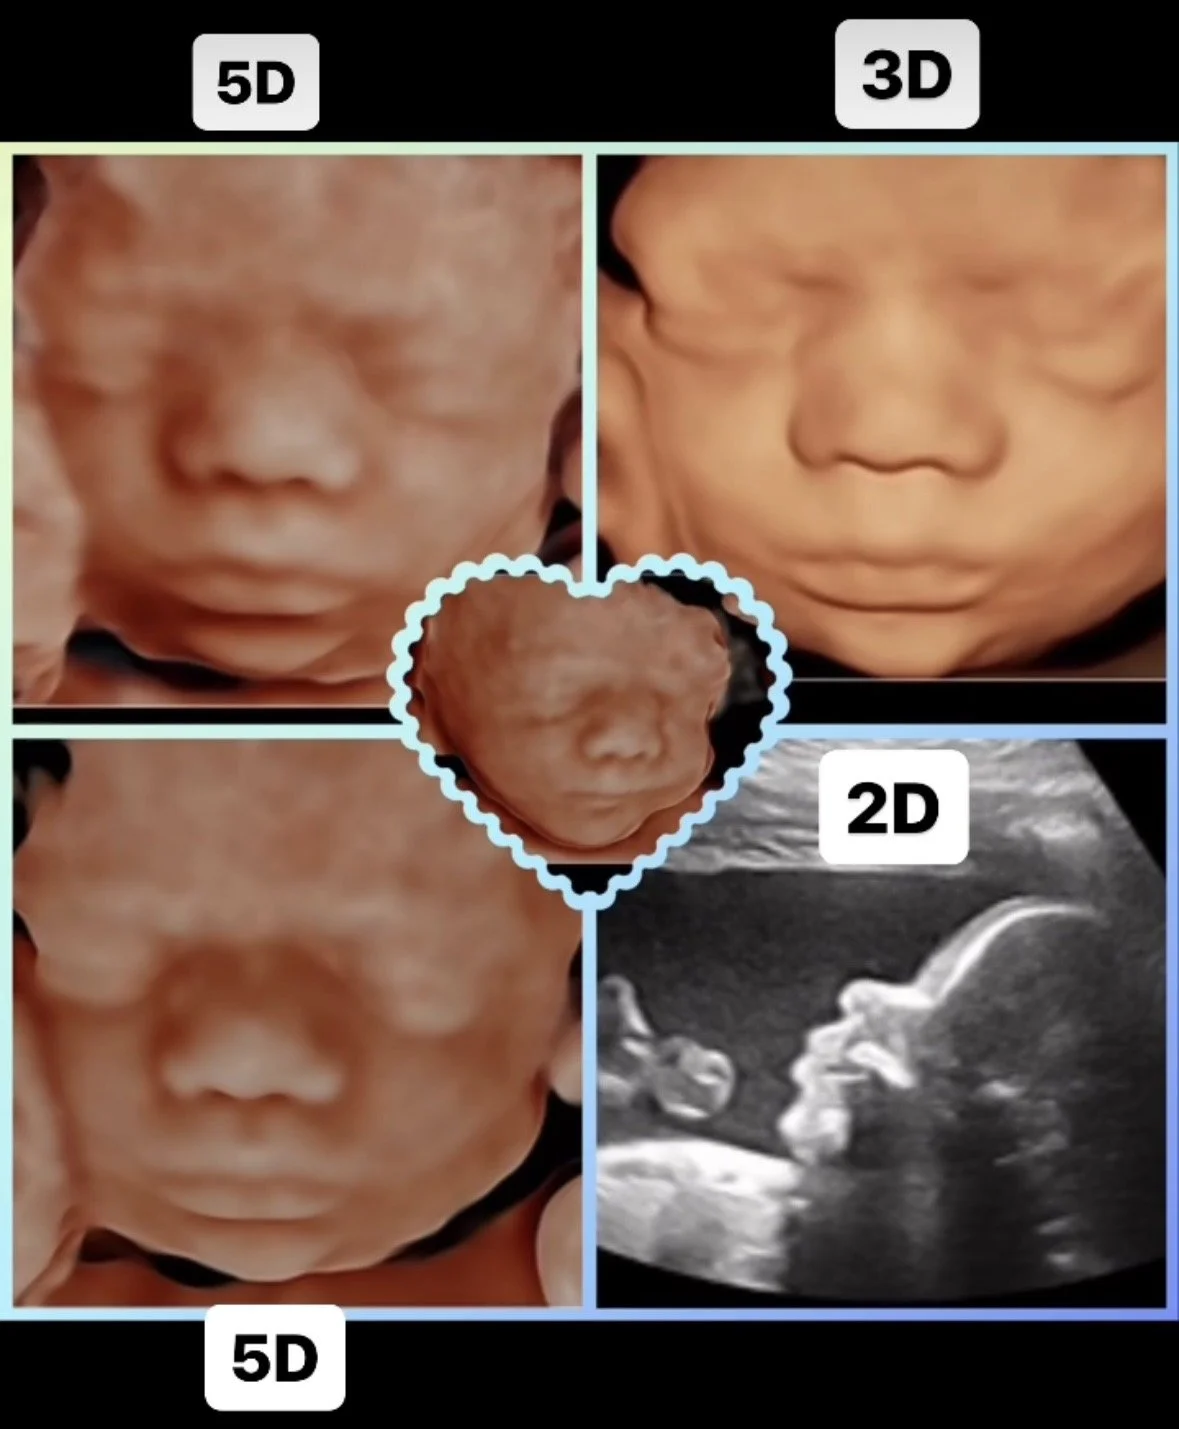

Naroopa is a Registered Diagnostic Medical Sonographer of 15 years, Author, and Entrepreneur in ultrasound business. She is the owner and Sonographer of Ultrasound Techniques,LLC; founded four years ago. She started her career as a technician, then moving into education, then her own business. She is very well experienced in ultrasound imaging and customer service. Naroopa promises VIP treatment and 3D/4D imaging services using brand new state of the art ultrasound equipment, a comfortable luxurious reclining bed, and professional decor and design. Your satisfaction is guaranteed!

This is a peek of where we scan our momma’s!